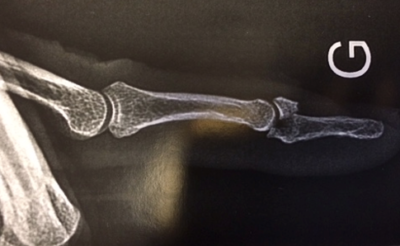

Des radiographies sont nécessaires afin de rechercher une fracture associée.

Le traumatisme est en général non douloureux mais vous allez remarquer la déformation qui est typique.Des radiographies sont nécessaires afin de rechercher une fracture associée.

Mallet finger osseux